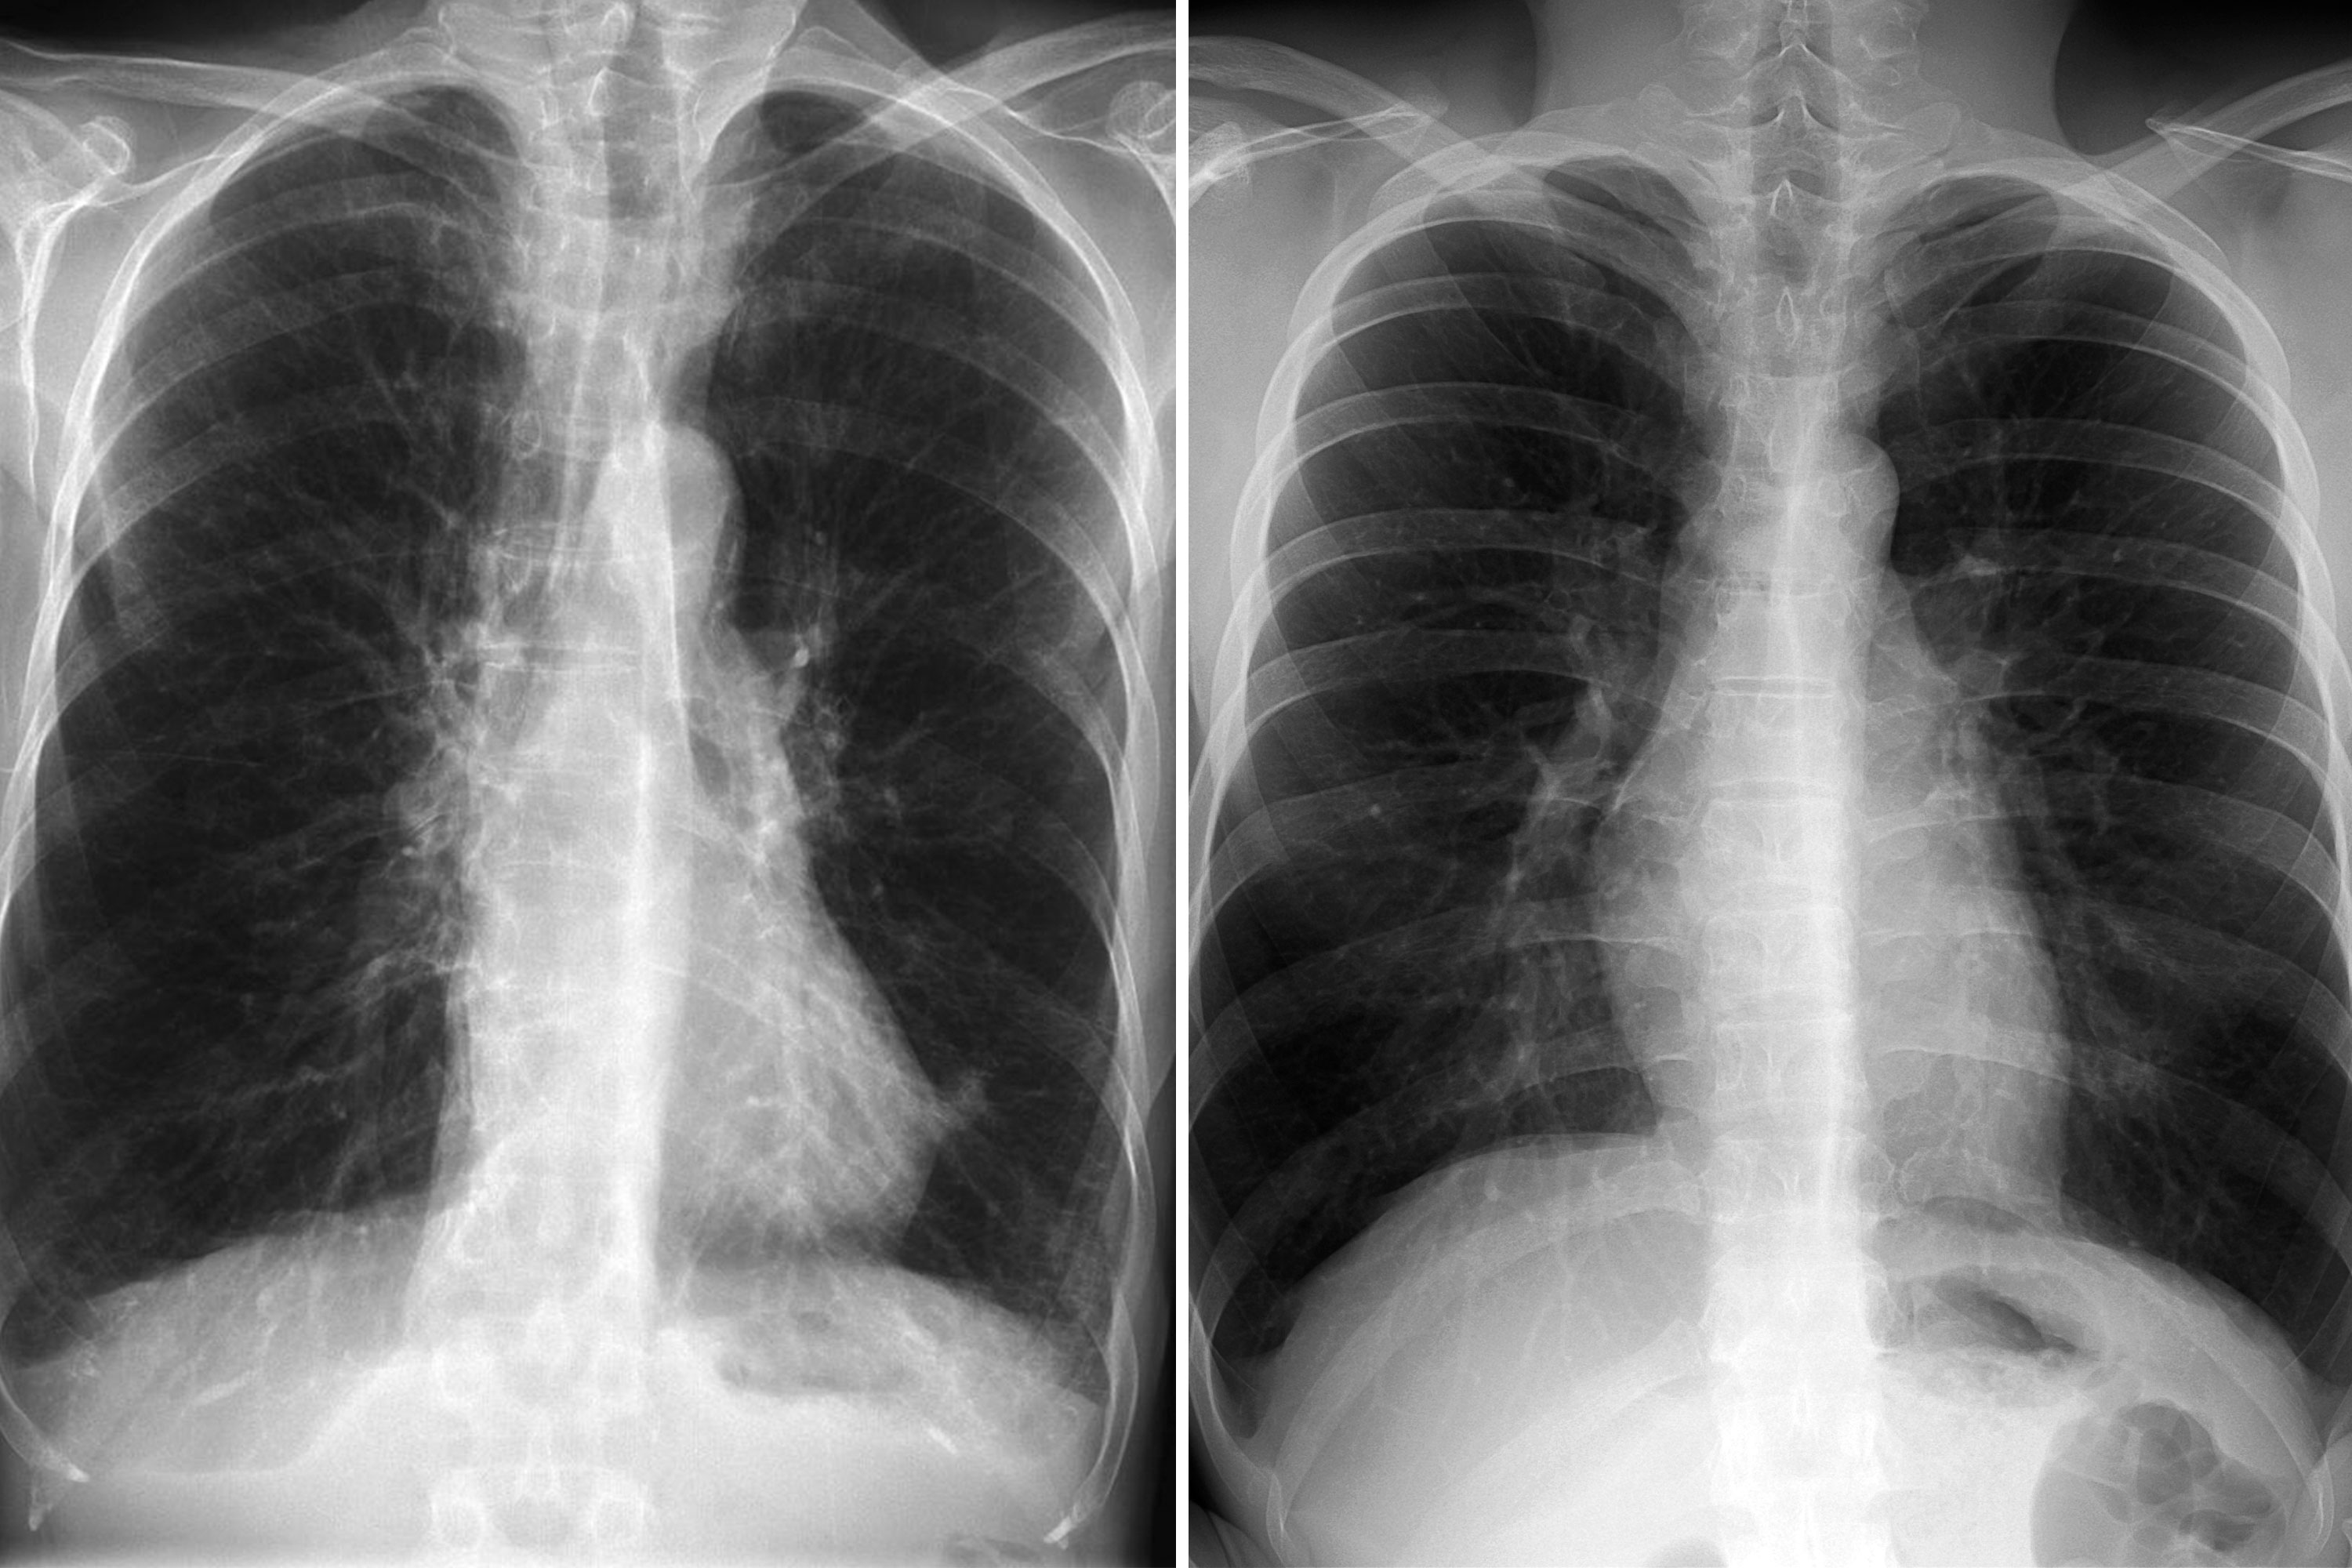

Experiencing chest pain from a muscle pull? Learn to identify symptoms of a strained pectoral muscle versus heart-related issues. Discover effective home remedies, gentle stretching techniques, and recovery tips to alleviate thoracic muscle strain and restore mobility. Get expert advice on when to seek medical attention for persistent chest discomfort and muscle injury relief.